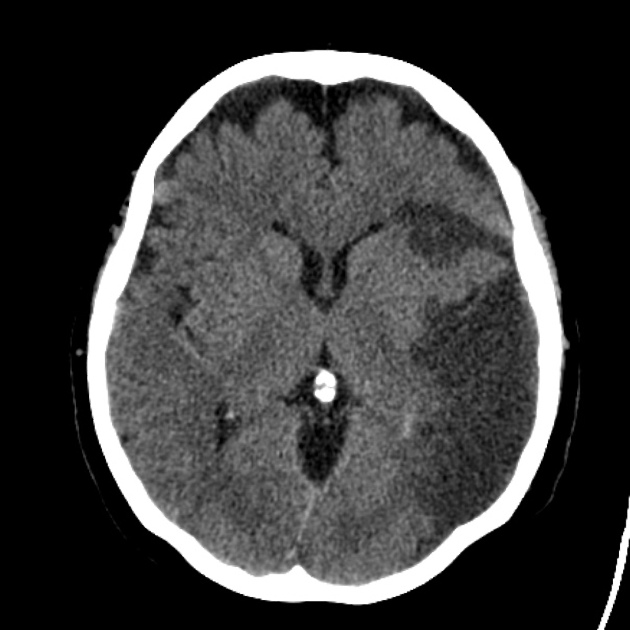

What Is ARIA?

ARIA stands for AmyloidRelated Imaging Abnormalities. It comes in two flavors: ARIAE (edema or swelling) and ARIAH (microhemorrhages). While many cases are asymptomatic, some patients feel headache, confusion, visual changes, or nausea.

Leqembi Side Effects ARIA

About 12% of patients develop ARIA on MRI during treatment. This is considerably lower than the rate seen with some other antiamyloid antibodies, but it still warrants close monitoring.

Monitoring Schedule

After the first infusion, a baseline MRI is required. Followup scans are done at weeks4,12, and then roughly every six months. Your radiologist will assess for any new edema or microbleeds and report back to your neurologist.

Managing ARIA

If ARIA is detected, doctors may hold the next dose, reduce the infusion rate, or give a short course of steroids. The infusion usually resumes once imaging and symptoms improve, following a clear protocol.